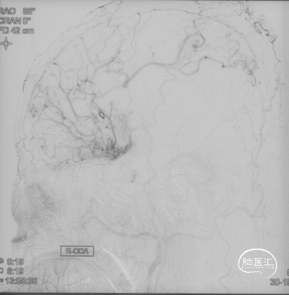

CTA和DSA

CTA和DSA所见:双侧颈内动脉闭塞,右侧椎动脉发出PICA后闭塞,左侧椎动脉V1-V2段闭塞。两条健壮的侧枝通过肌支吻合汇入左椎动脉V2段,构成了整个大脑大部分供血的主要来源。双侧颈外动脉亦有少量血流供应颅内。这样的颅内供血很容易发生失代偿,导致TIA甚至脑梗。